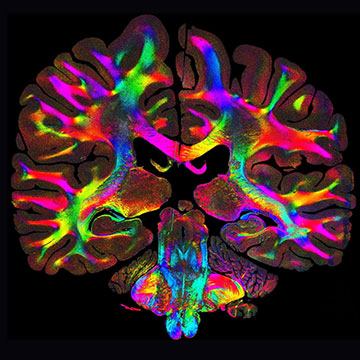

A new imaging technique can map out the orientation and organization of tissue fibers at the microscale. The colors represent different fiber orientations. [Image: Marios Georgiadis/Stanford]

In contrast, the new technique, called computational scattered light imaging (ComSLI), can produce high-resolution images of specimens created using any preparation method, including those that have been preserved and stored for decades. The only equipment needed is a rotating LED lamp and a standard microscope camera, which record the light scattered from the sample at different angles. Most of the light is scattered perpendicular to the main axis of the fibers, allowing the light patterns to be translated into a color-coded image that maps out the orientation and density of the fibers with micrometer resolution.